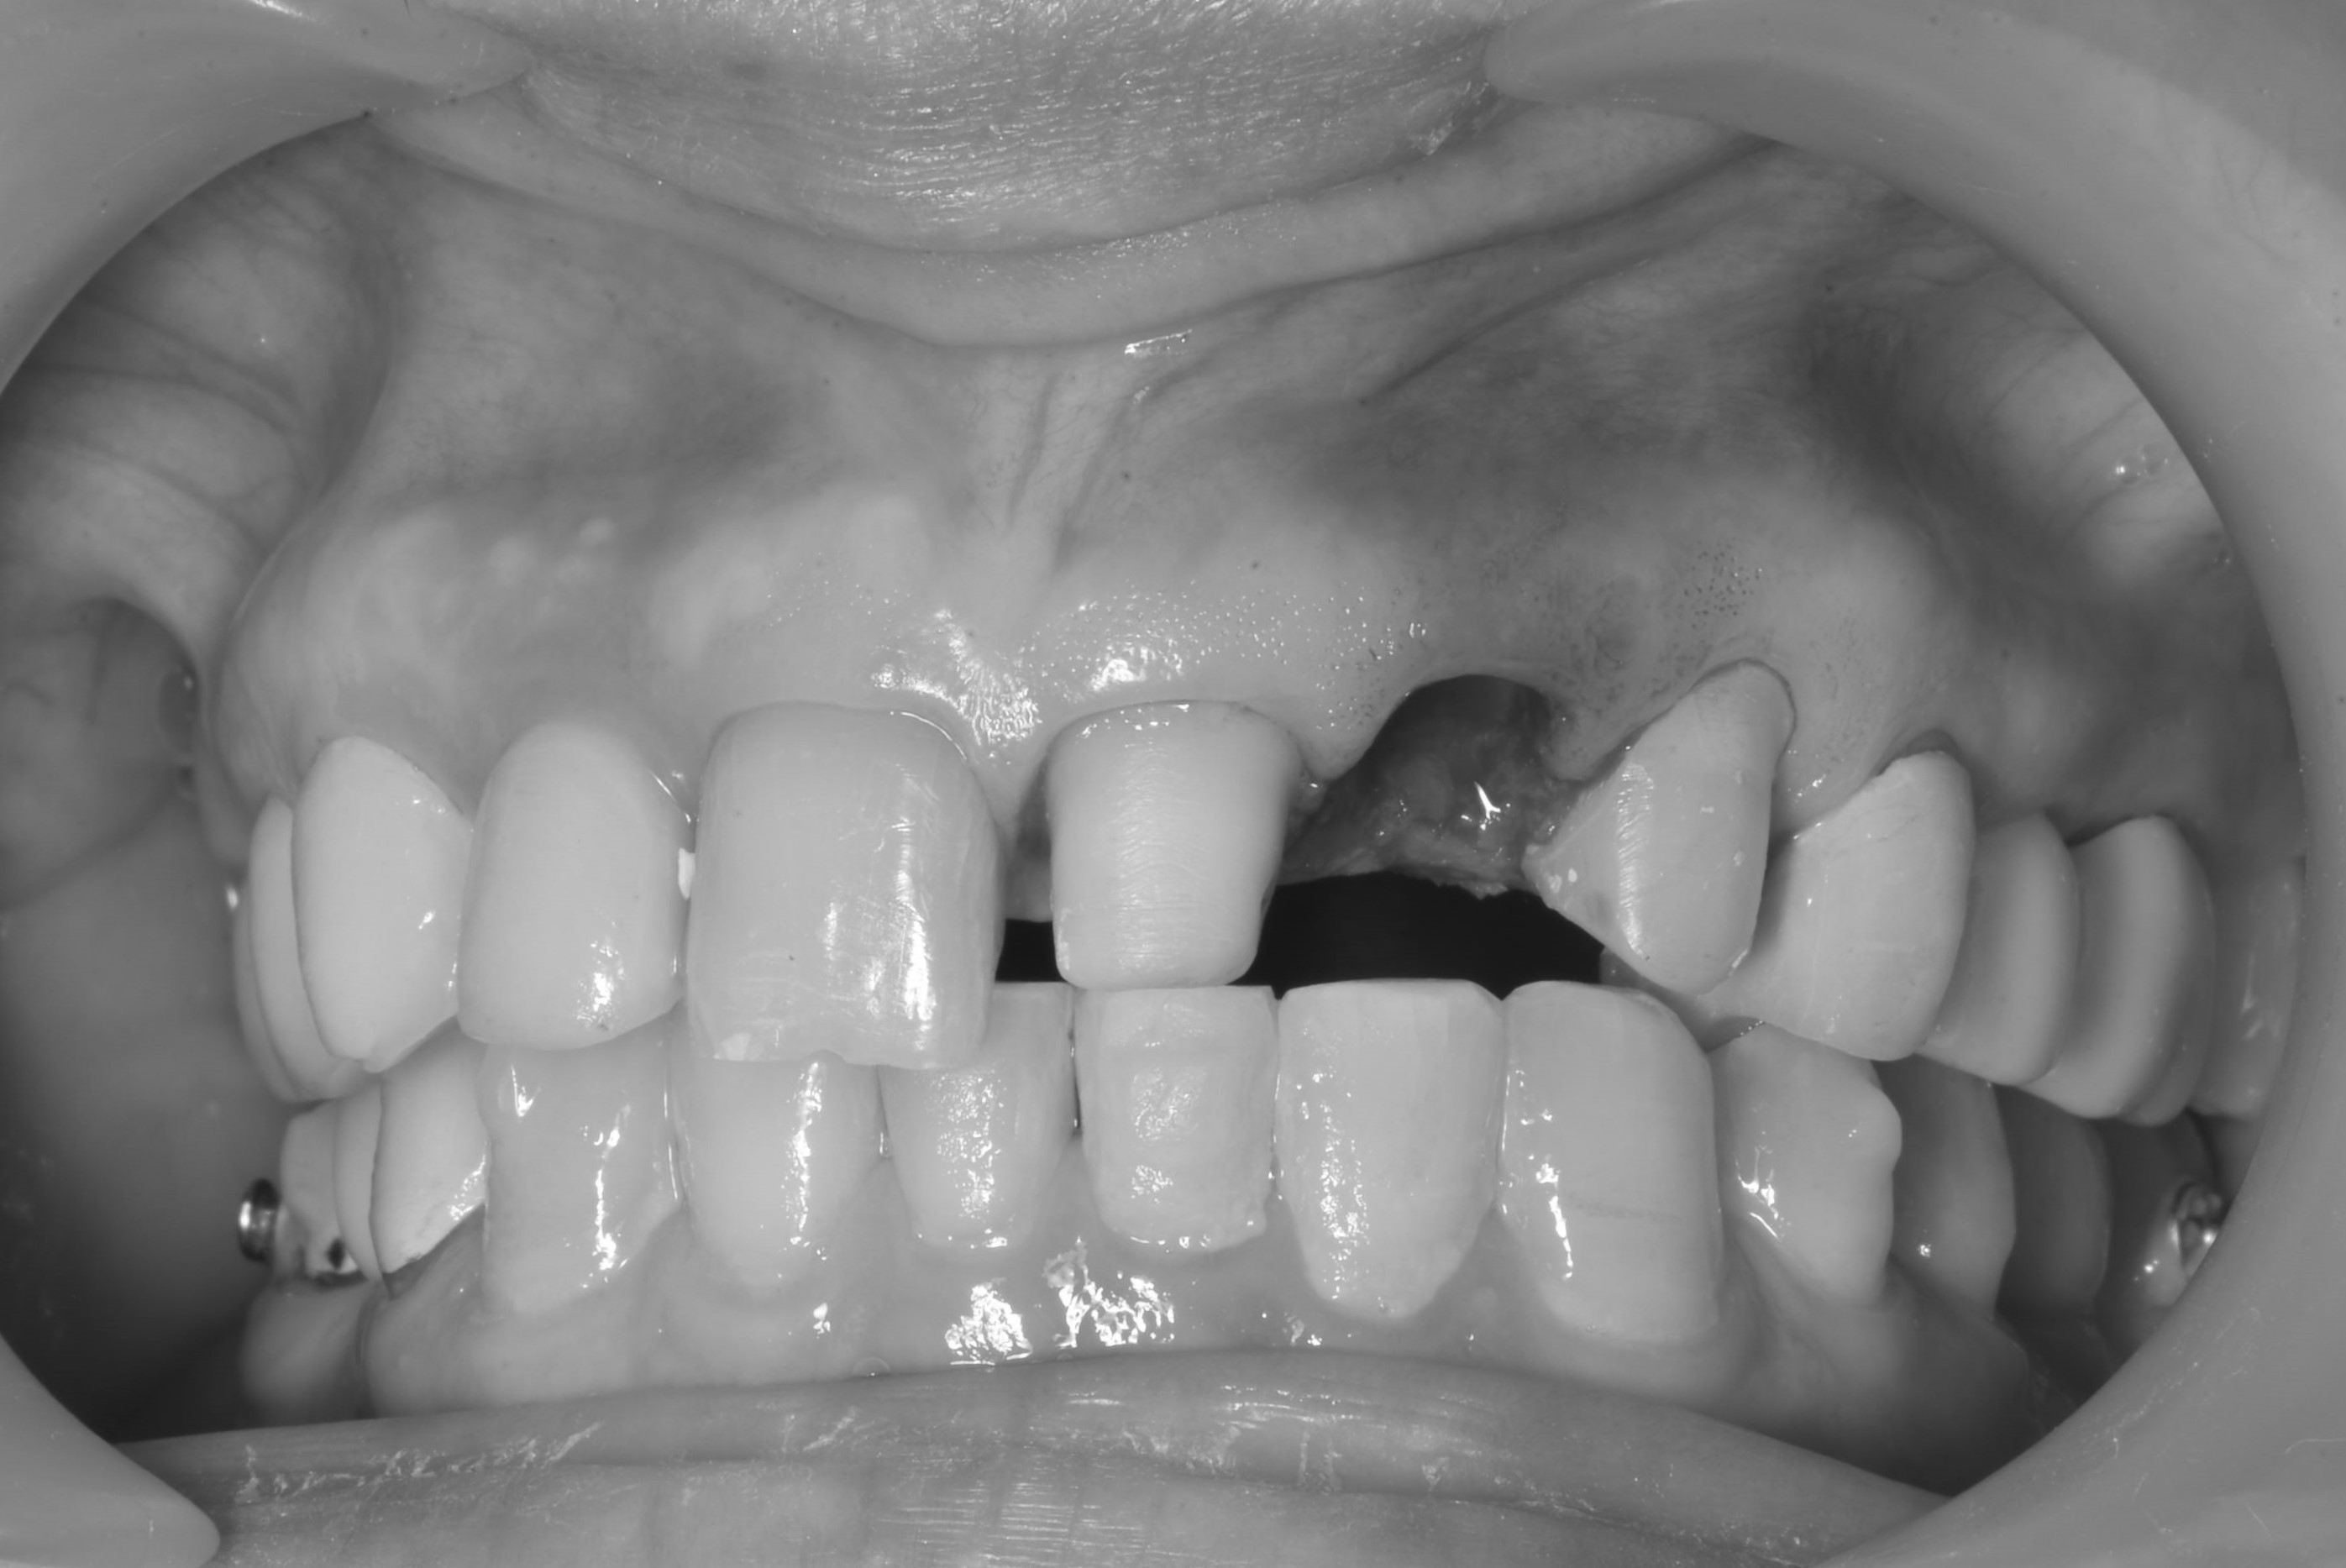

前牙美學植牙